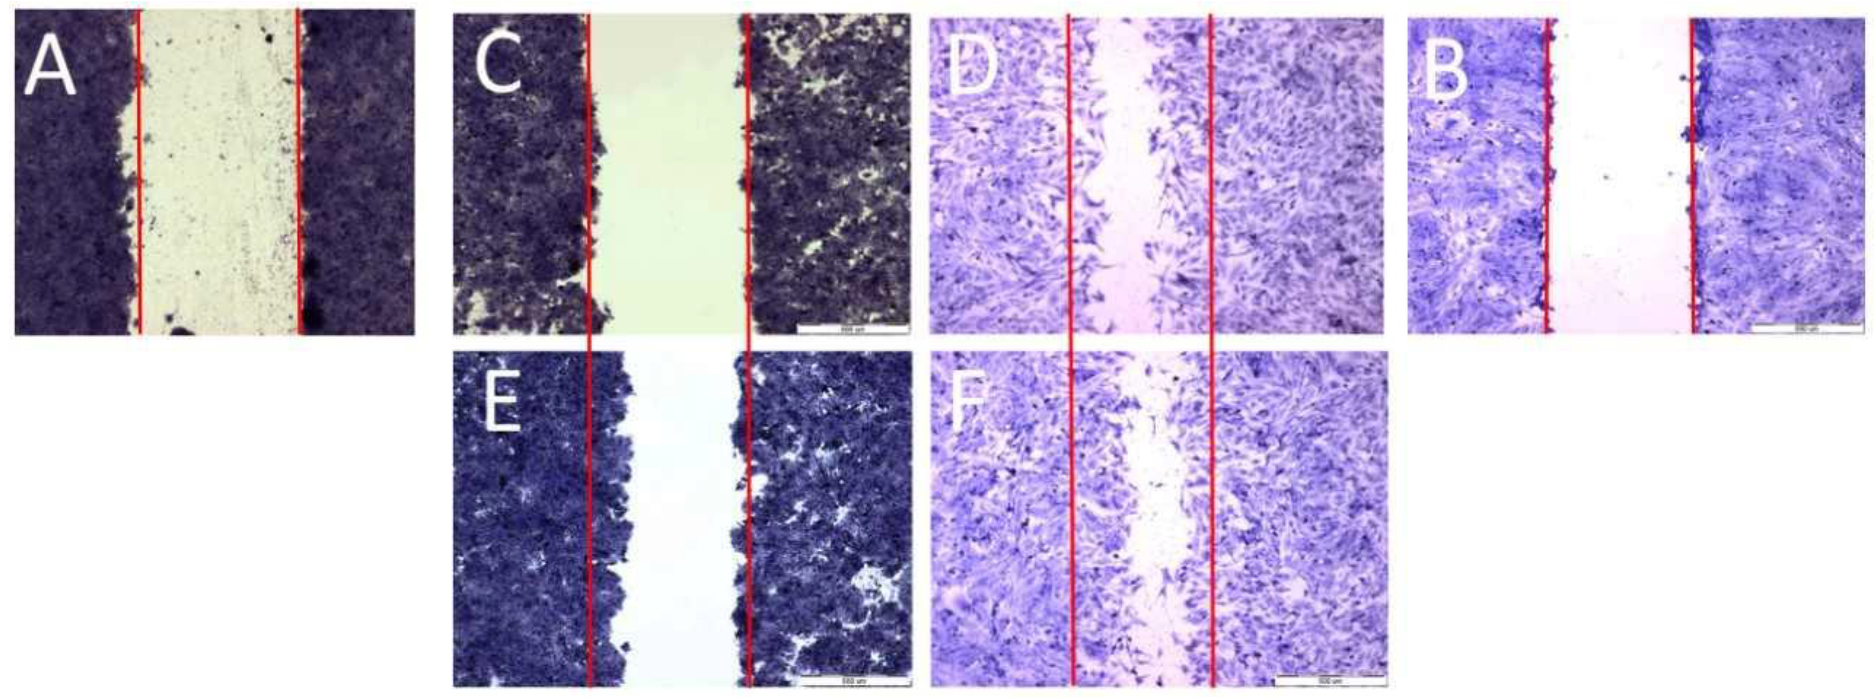

To examine cell migration, three parallel experiments were performed: a scratch assay, a circle assay (horizontal migration) and a vertical migration analysis. Horizontal migration is presented in Figure 4 (scratch assay) and Figure 5 (circle assay).

Figure 4.

Scratch assay; scratch control: (A)—HT29, (B)—CCD 841 CoTr; control 24 h: (C)—HT29 and (D)—CCD 841 CoTr; scratch after 24 h: (E)—HT29 and (F)—CCD 841 CoTr. Bar = 500 μm.

Both horizontal migration assays confirmed the HT29 cell line’s low mobility in the presence of porphyrins (Figure 6A,C and Figure 7A,C). The analyzed concentrations of porphyrins did not significantly influence the migration of cancer cells. In the case of the CCD 841 CoTr cells, both analyzed compounds significantly inhibited migration when combined with white light irradiation (Figure 6B,D and Figure 7B,D).